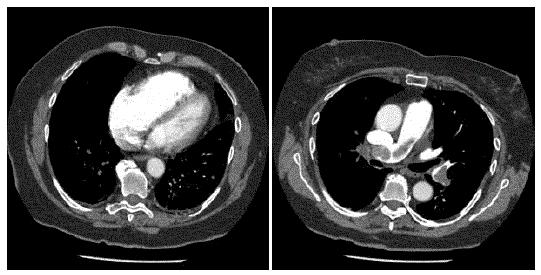

Mulher de 32 anos vem ao Pronto-Socorro com queixa de dispneia súbita há um dia, após viagem aérea de 12 horas. Nega comorbidades. Exame clínico: PA = 80 x 40 mmHg; FC = 140 bpm; FR = 28 ipm; T = 37,8ºC. Lúcida, orientada. Perfusão periférica regular (enchimento capilar = 4 s). Exame clínico sem outras alterações. Foi feita hipótese diagnóstica de tromboembolismo pulmonar e realizado eletrocardiograma (taquicardia sinusal) e angio-tomografia de tórax (abaixo).

A conduta inicial mais apropriada neste momento é: